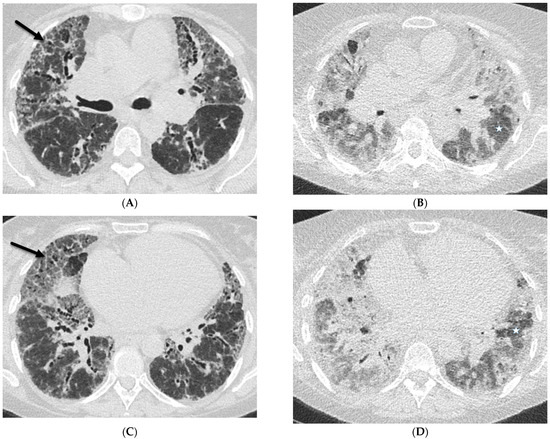

2.1. COVID-19 Pneumonia

2.4. Pneumocystis Jiroveci Pneumonia (PJP)